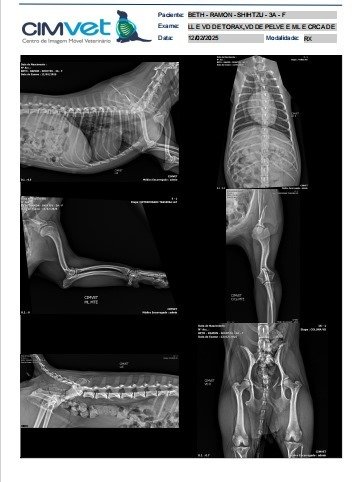

Meu nome é Naiara, minha cachorrinha foi atacada e se machucou muito, quebrou alguns ossos incluindo a escapula e a pelvis e por isso precisa de cirurgia que no total ficou 2.835, e por isso preciso da sua ajuda. ver tudo

Meu nome é Naiara, minha cachorrinha foi atacada e se machucou muito, quebrou alguns ossos incluindo a escapula e a pelvis e por isso precisa de cirurgia que no total ficou 2.835, e por isso preciso da sua ajuda.